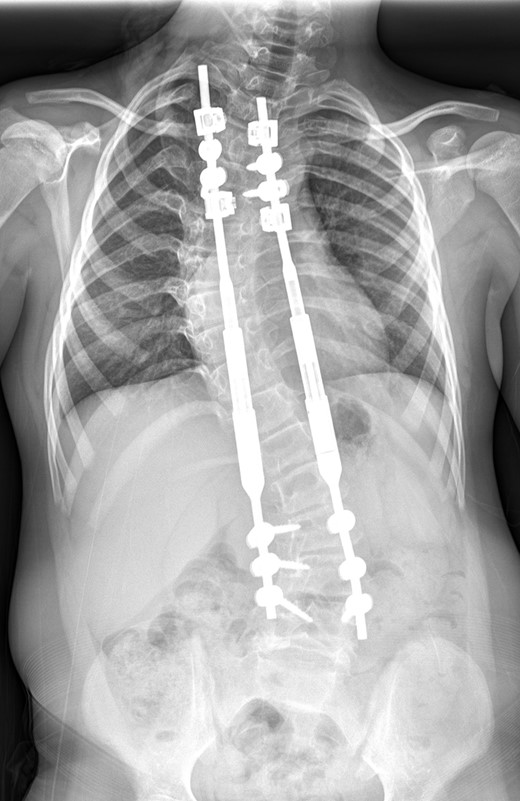

Subsequent transcutaneous, magnetic spinal lengthening has been performed on six occasions in the outpatient setting over the last 2 years. This has been uncomplicated and has not been associated with significant pain or fracture. She takes paracetamol after each magnetic lengthening procedure, easing mild muscular discomfort. The control of the scoliosis has been maintained, and at 2 years post-insertion of MCGR the spinal curves now measure 40° for the thoracic curve and 37° for the thoracolumbar curve with a T1–S1 height of 288 mm and T1–T12 height of 195 mm (Fig. 3). The MCGR have been lengthened by 16 mm on either side.

A whole spine radiograph at age 8 following multiple lengthening procedures showing elongation of the MCGR rods (measuring 40° for the thoracic curve and 37° for the thoracolumbar curve with a T1–S1 height of 288 mm and T1–T12 height of 195 mm).